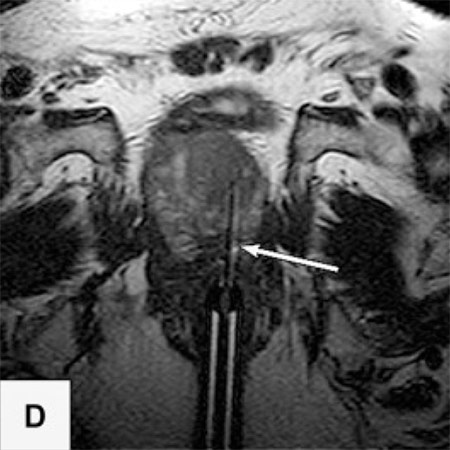

Die Probleme der Fusionsbiopsie und der Unsichtbarkeit von Krebsherden im Ultraschall lassen sich auf elegante Weise vermeiden, wenn die Biopsie direkt MRT-gesteuert im Kernspintomographen selbst ausgeführt wird.

In der Vitus Privatklinik nutzen wir diese Möglichkeit der präzisen, direkt durch MRT-Bilder gesteuerten Biopsie. Dazu wird die Biopsienadel entweder manuell oder mit einem Soteria Biopsie-Roboter in den verdächtigen Herd gesteuert, unter direkter MRT-Kontrolle. Dies ermöglicht es, mit hoher Präzision, die Biopsienadel direkt in den verdächtigen Herd in der Prostata zu steuern. Dort angekommen kann die Biopsie im MRT direkt verfolgt werden, und nach der Probenentnahme durch die Darstellung des Stichkanales überprüft werden, ob der Herd getroffen wurde. Auf diese Weise können auch kleine Karzinomherde mit hoher Sicherheit biopsiert werden2.